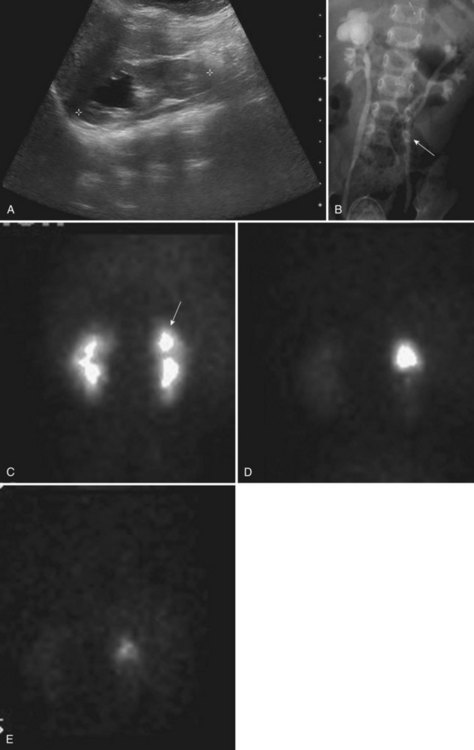

Hydrocalycosis is a very rare cystic dilation of a major calyx with a demonstrable connection to the renal pelvis (Fig. 117–20). It may be caused by a congenital or acquired intrinsic obstruction, such as a parapelvic cyst.

Figure 117–20 Two-month-old girl with prenatal history of right upper pole renal cyst. A, Sagittal ultrasonogram shows right kidney and a 2.5-cm cystic structure in the right upper pole (space between calipers denotes renal length). B, Voiding cystourethrogram demonstrates bilateral vesicoureteral reflux with marked dilation of the right upper pole compound calyx suggestive of hydrocalycosis. Note on the right, triplication of the pelvis, and, on the left, early division of the ureter (arrow) with triplication of the pelvis associated with the uppermost ureter. C, MAG3 scan in prone view shows prompt symmetrical uptake of the isotope. D, Prefurosemide injection with retained isotope in right upper pole compound calyx. E, Prompt drainage of the calyx following furosemide injection.

Dilation of the upper calyx due to obstruction of the upper infundibulum by vessels or stenosis has been described (Fraley, 1966; Johnston and Sandomirsky, 1972). Cicatrization of an infundibulum may result from infection or trauma. Conversely, hydrocalycosis has been reported to occur without an obvious cause (Williams and Mininberg, 1968). It has been postulated that achalasia of a ring of muscle at the entrance of the infundibulum into the renal pelvis causes a functional obstruction (Moore, 1950; Williams and Mininberg, 1968).

Mild upper calyceal dilation caused by partial infundibular obstruction is relatively common but usually asymptomatic. Although the most frequent presenting symptom is upper abdominal or flank pain, hydrocalycosis may be detected on prenatal ultrasonography (see Fig. 117–20). On occasion, a mass may be palpated. Stasis can lead to hematuria or urinary infection, or both.